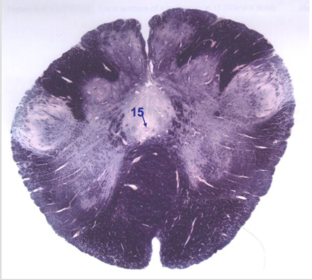

| Nucleus gracilis | |

| Accessory nucleus | |

| Medial longitudinal faciculus | |

| Pyramidal decussation | |

| Medullary pyramids | |

| Anterior spinocerebellar tract | |

| ALS | |

| Posterior spinocerebellar tract | |

| Spinal tract of V | |

| Spinal nucleus of V | |

| Nucleus cuneatus | |

| Fasciculus cuneatus | |

| Fasciculus gracilis | |

| Central canal | |